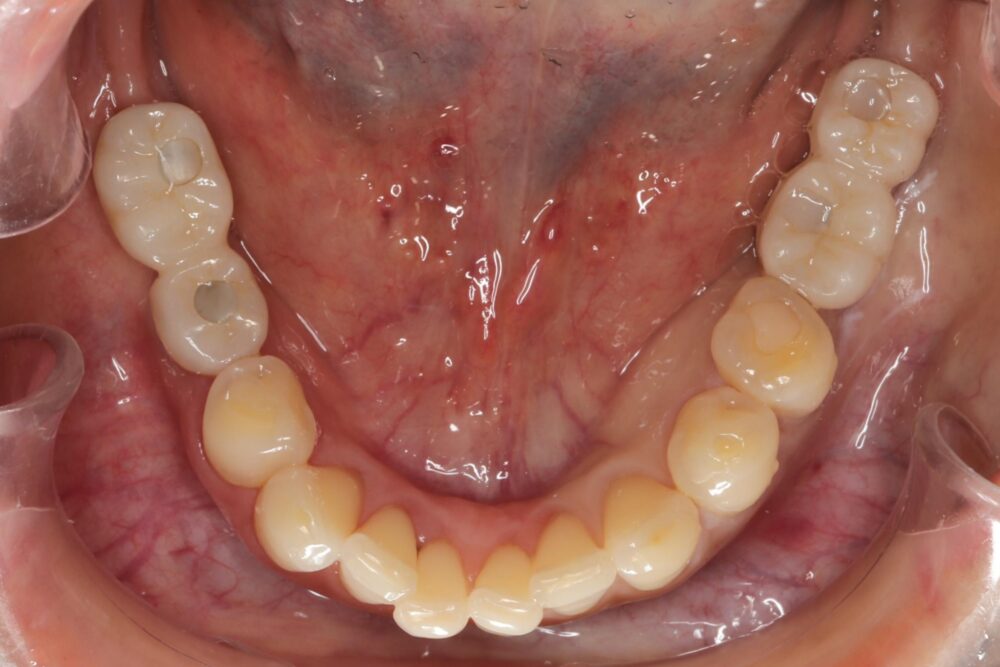

症例11

50代 男性 なんでも食べられるようになりたい

術前咬合面

術前咬合面

術後咬合面

術後咬合面

| 主訴 | 自分が一番元気に、何でも食べられる父親でいたい。家族との食事の時間が人生ですごく大切で、何とかしたい、と思っていた。 |

| 年代・性別 | 50代 男性 |

| 治療部位 | 上顎6~6 |

| 手術回数 | 1回 |

| 治療期間 | 4ヶ月 |

| 手術時間 | 180分 |

| 治療回数 | 10回 |